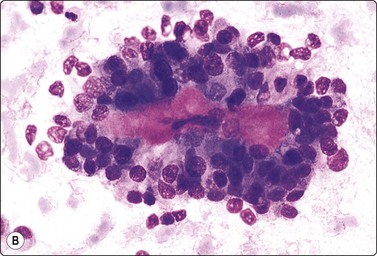

image image

Fig. 11.18 Islet cell tumor

(A) Poorly cohesive sheets and dispersal; cells with oval nuclei, stippled chromatin and small nucleoli (Pap, IP); (B) Mainly dispersed cells with uniformly round nuclei, speckled chromatin, moderate anisokaryosis; delicate cytoplasm; a suggestion of pseudorosettes (MGG, HP).

Criteria for diagnosis

Many single and loosely grouped cells, pseudorosettes,

Rounded monotonous nuclei, mild to moderate anisokaryosis,

Speckled chromatin and 1–3 small nucleoli,

Poorly defined, finely granular cytoplasm, often dispersed in the background,

Nuclei eccentric if cytoplasm intact.

These functional or nonfunctioning tumors of adults are situated mainly in the body and tail of the pancreas. The tumors are well within the scope of EUS cytodiagnosis.114,115 The neoplastic cells are mainly dissociated, but often form loose acinar or follicular clusters and curved or circular rows (Fig. 11.18). In the majority of cases, nuclei are characteristically round to oval and uniformly small. Occasionally, nuclear anisokaryosis may be prominent, but the nuclear chromatin pattern varies little between cells. The chromatin is evenly distributed, coarsely granular or ‘speckled’. The small nucleoli are not easily seen in Giemsa-stained smears. Due to its fragility, the cytoplasm is often dispersed in the background. When it is preserved, nuclei are eccentrically situated within defined cell borders. A very fine, red granularity is often discernible in MGG smears with high magnification. Clumps of amyloid may occasionally be seen, but necrosis is not observed.113,116-119 The cytological pattern of most islet cell tumors is sufficiently characteristic to be easily distinguished from that of pancreatic adenocarcinoma. Production and secretion of specific hormone products cannot be distinguished on the basis of routine cytological smears alone. If the secretory products of the neoplastic cells can be identified by immunocytochemical methods, a more specific diagnosis can be made with confidence. General neuroendocrine markers will usually be positive, such as neuron-specific enolase, synaptophysin, chromogranin-A, PGP9.5 and CD56. Specific secretory products, e.g. insulin can be marked by appropriate antibodies but this does not necessarily correlate with raised serum levels. Electron microscopy will demonstrate dense-core neurosecretory granules. A decision on whether a tumor is benign or malignant is problematic. Even histopathology is poorly predictive of aggressive behavior. In general, nuclear atypia and pleomorphism cannot be relied on as cytological criteria of malignancy (Fig. 11.20). More aggressive behavior correlates with a raised proliferation index assessed using Ki-67 immunohistochemistry (> 2%).120 This is a parameter in the WHO 2004 histology based-grading system.121,122 Only documentation of metastasis finally provides proof of malignancy.123,124